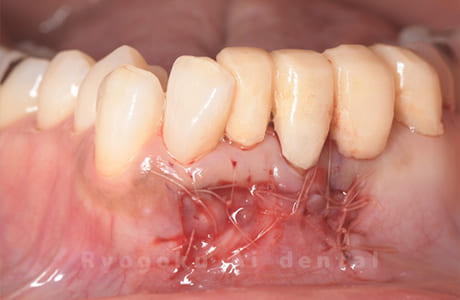

歯根端切除術中

-

歯根端切除術直後

歯根端切除術後

- 原因

- パーフォレーション、慢性根尖性歯周炎

- 治療内容

- マイクロエンド、MTM、クラウンレングスニング、歯根端切除術

- 治療費用

- 286,000円

他院で歯の根の中に穴が空いているとのことで抜歯と診断された患者様です。一部穴が空いている部分を修復し、部分矯正を行い、手術を行いました。経過良好で、患者様も満足されています